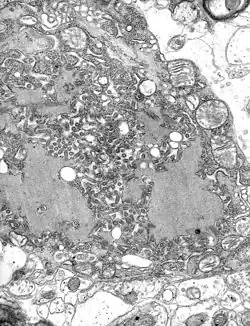

Buruli ulcer is caused by the bacterium Mycobacterium ulcerans.[33] It is related to the bacteria that cause tuberculosis and leprosy. Mycobacterium ulcerans produces a toxin, mycolactone, that destroys tissue.[33] The prevalence of Buruli ulcer is unknown.[17] The risk of mortality is low, although secondary infections can be lethal.[34] Morbidity takes the form of deformity, disability, and skin lesions, which can be prevented through early treatment with antibiotics and surgery.[34] It is found in Africa, Asia, Australia,[35] and Latin America.[36]